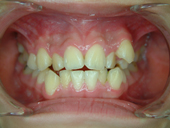

圖七、車禍導致牙齒脫落及斷裂

圖八、經過矯正(空間重新分部)及假牙製作

導致牙齒排列不整的原因包羅萬象,情況也是千奇百怪。有的人是因為牙齒大小和牙床大小不諧調,導致齒列擁擠(圖一、二)或是產生縫隙,台灣人最介意的“牙齒漏財”即屬於縫隙這個類型(圖三、四);有的人則是牙齒長到不該長的位置而沒有冒出牙床(圖五、六);有些人則是上下顎骨發育不諧調,導致戽斗(或稱月亮臉)或是鳥臉的狀況;除此之外,暴牙、先天缺牙、多生牙、後天蛀牙或長期缺牙導致相鄰牙齒東倒西歪、車禍外傷導致牙齒移位或喪失牙齒(圖七、八)、牙周病所導致的門牙散開…等等,都是齒顎矯正的適應症。